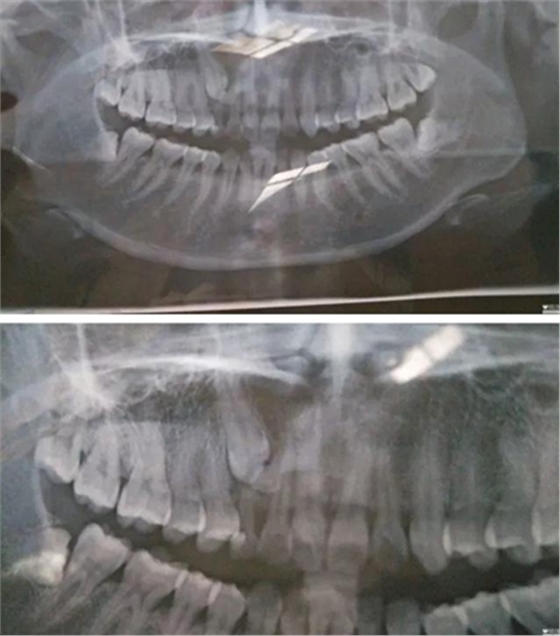

2017年6月18日,牙疼…之前補過一次,這次估計是發(fā)炎了,然后被伊森告知乳牙滯留,恒牙阻生,要拍片確認(rèn)恒牙是否完好,才能進(jìn)行下一步…鎮(zhèn)醫(yī)院,設(shè)備不齊全,伊森建議去大醫(yī)院拍片…

心里著急,第二天就跑到廣東省口腔醫(yī)院花了一天的時間排隊拍片,然后被伊森建議去矯正科詳細(xì)咨詢…然后矯正伊森就跟我說了大概治療方案,時間和費用,先拔掉四顆智慧牙,然后帶牙套矯正牙齒,期間會拔掉小虎牙給埋伏牙做牽引(我情況比較復(fù)雜,下面有兩顆埋伏牙,還得拔掉其中一顆)╭(°A°`)╮而且還不一定牽引成功,如果不成功,最后矯正后期還要種植牙齒(?_?)…要花3-4W,長達(dá)2年時間…當(dāng)時就震驚了,從沒想過自己這口牙辣么貴,辣么麻煩…

跟LG一起確定了矯正之后,立馬打電話給伊森預(yù)約了7.3號,然后LG陪我一起去了醫(yī)院,伊森詳細(xì)了解了婚姻狀況,生娃狀況(對于我已經(jīng)有兩個娃的事實表示了各種驚訝),然后拍片,倒模具,定制方案,約定下次就診時間…

然后被伊森告知了一個不好的消息,(?_?)我乳牙下面的牙經(jīng)集體開會討論一直認(rèn)為牽引不上來,需要矯正完成后去種植,費用要1-1.5W,瞬間心都涼了T^T,期間繼續(xù)不死心的重復(fù)問可不可以牽引,估計所有人都會覺得牙齒還是原配的好…結(jié)果還是令我失望〒_〒